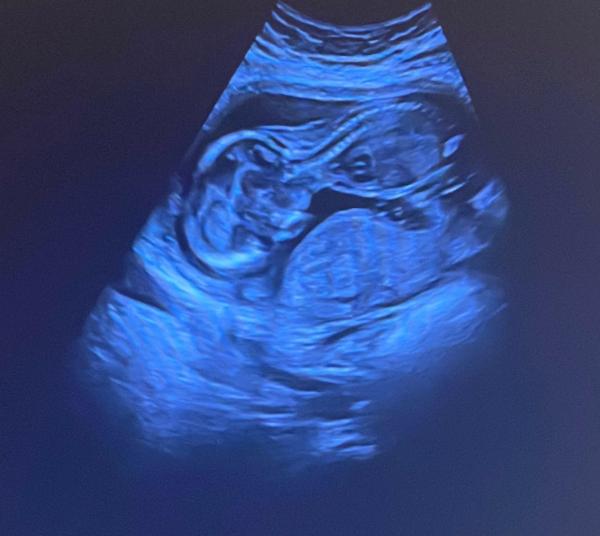

Hi zusammen, manchmal kommt mir die Schwangerenvorsorge ein bisschen vor wie ein Krimi. Hier mal so ne kleine Story, was mir so passiert. 😅 War heute beim FA und nach dem der keine rechtzeitigen Termin für's Ersttrimesterscreening hatte, war ich eben erst heute bei 14+4 da. Lief auch alles erst supi, direkt Urin abgegeben, anschließend gleich Blutdruck und Gewicht gemessen. Gefühlt 5 Minuten später schon beim FA. Nachdem ich keine Fragen oder so hatte, konnten wir direkt loslegen. Aaaaber, er wollte nur eine vaginale Untersuchung machen und ich wollte genau das nicht, sondern nur einen Ultraschall. Naja, bisschen diskutiererei hat er dann den Ultraschall gemacht, aber wie!!! Mein Mann meinte, wie beim Militär! Herz schlägt, Wirbelsäule ... so wurde zackig, eines nach dem anderen abgecheckt. Meine Kids haben mit leuchtenden Augen auf den Monitor gestarrt. Und ich habe sogar 2 Fotos bekommen. 😁 Hat aber glaube auch alles nur ca. 5 Minuten gedauert. Sowas habe ich in den letzten 2 Schwangerschaften auch noch nicht erlebt. 🤷🏻‍♀️ Ich habe dann (dachte ich zumindest 🤔) 2 Hebammen. Weil die erste, die ich aus meiner letzten ss kannte ruhiger machen wollte wegen der Rente und deswegen auch erst nach der 12. Woche treffen wollte. Diese war jetzt auf einmal mega beleidigt, das ich mir noch eine andere Hebamme gesucht hatte, weil ich eben die Vorsorge nicht durch nen Arzt sondern die Hebammen machen wollte. FA nur für US. Die hat mir ernsthaft per WhatsApp ein Ultimatum gestellt, a la, entweder die oder ich! Die andere hat so ähnlich reagiert. 😱 Was geht'n da ab? Im Vorfeld hatte ich beide gefragt und es hieß kein Problem auch Hebammen können im wechsel. Jetzt hieß es auf einmal FA und Hebamme im Wechsel geht, aber Hebamme und Hebamme geht nicht. 🙄 Aber die Schwangeren und ihre Hormone. 😉🤣 Wer das alles auch irrekomisch findet und wissen mag, wie es weiter geht. Schreibt mir gerne ein Kommentar. 🤗 P.S. hoffe das Bild anhängen hat geklappt. Ich finde allerdings es sieht etwas unvorteilhaft aus. 🤷🏻‍♀️🤭

Bild zu FA-Termin und Hebammen(krieg?) - Forum für März - Mamis